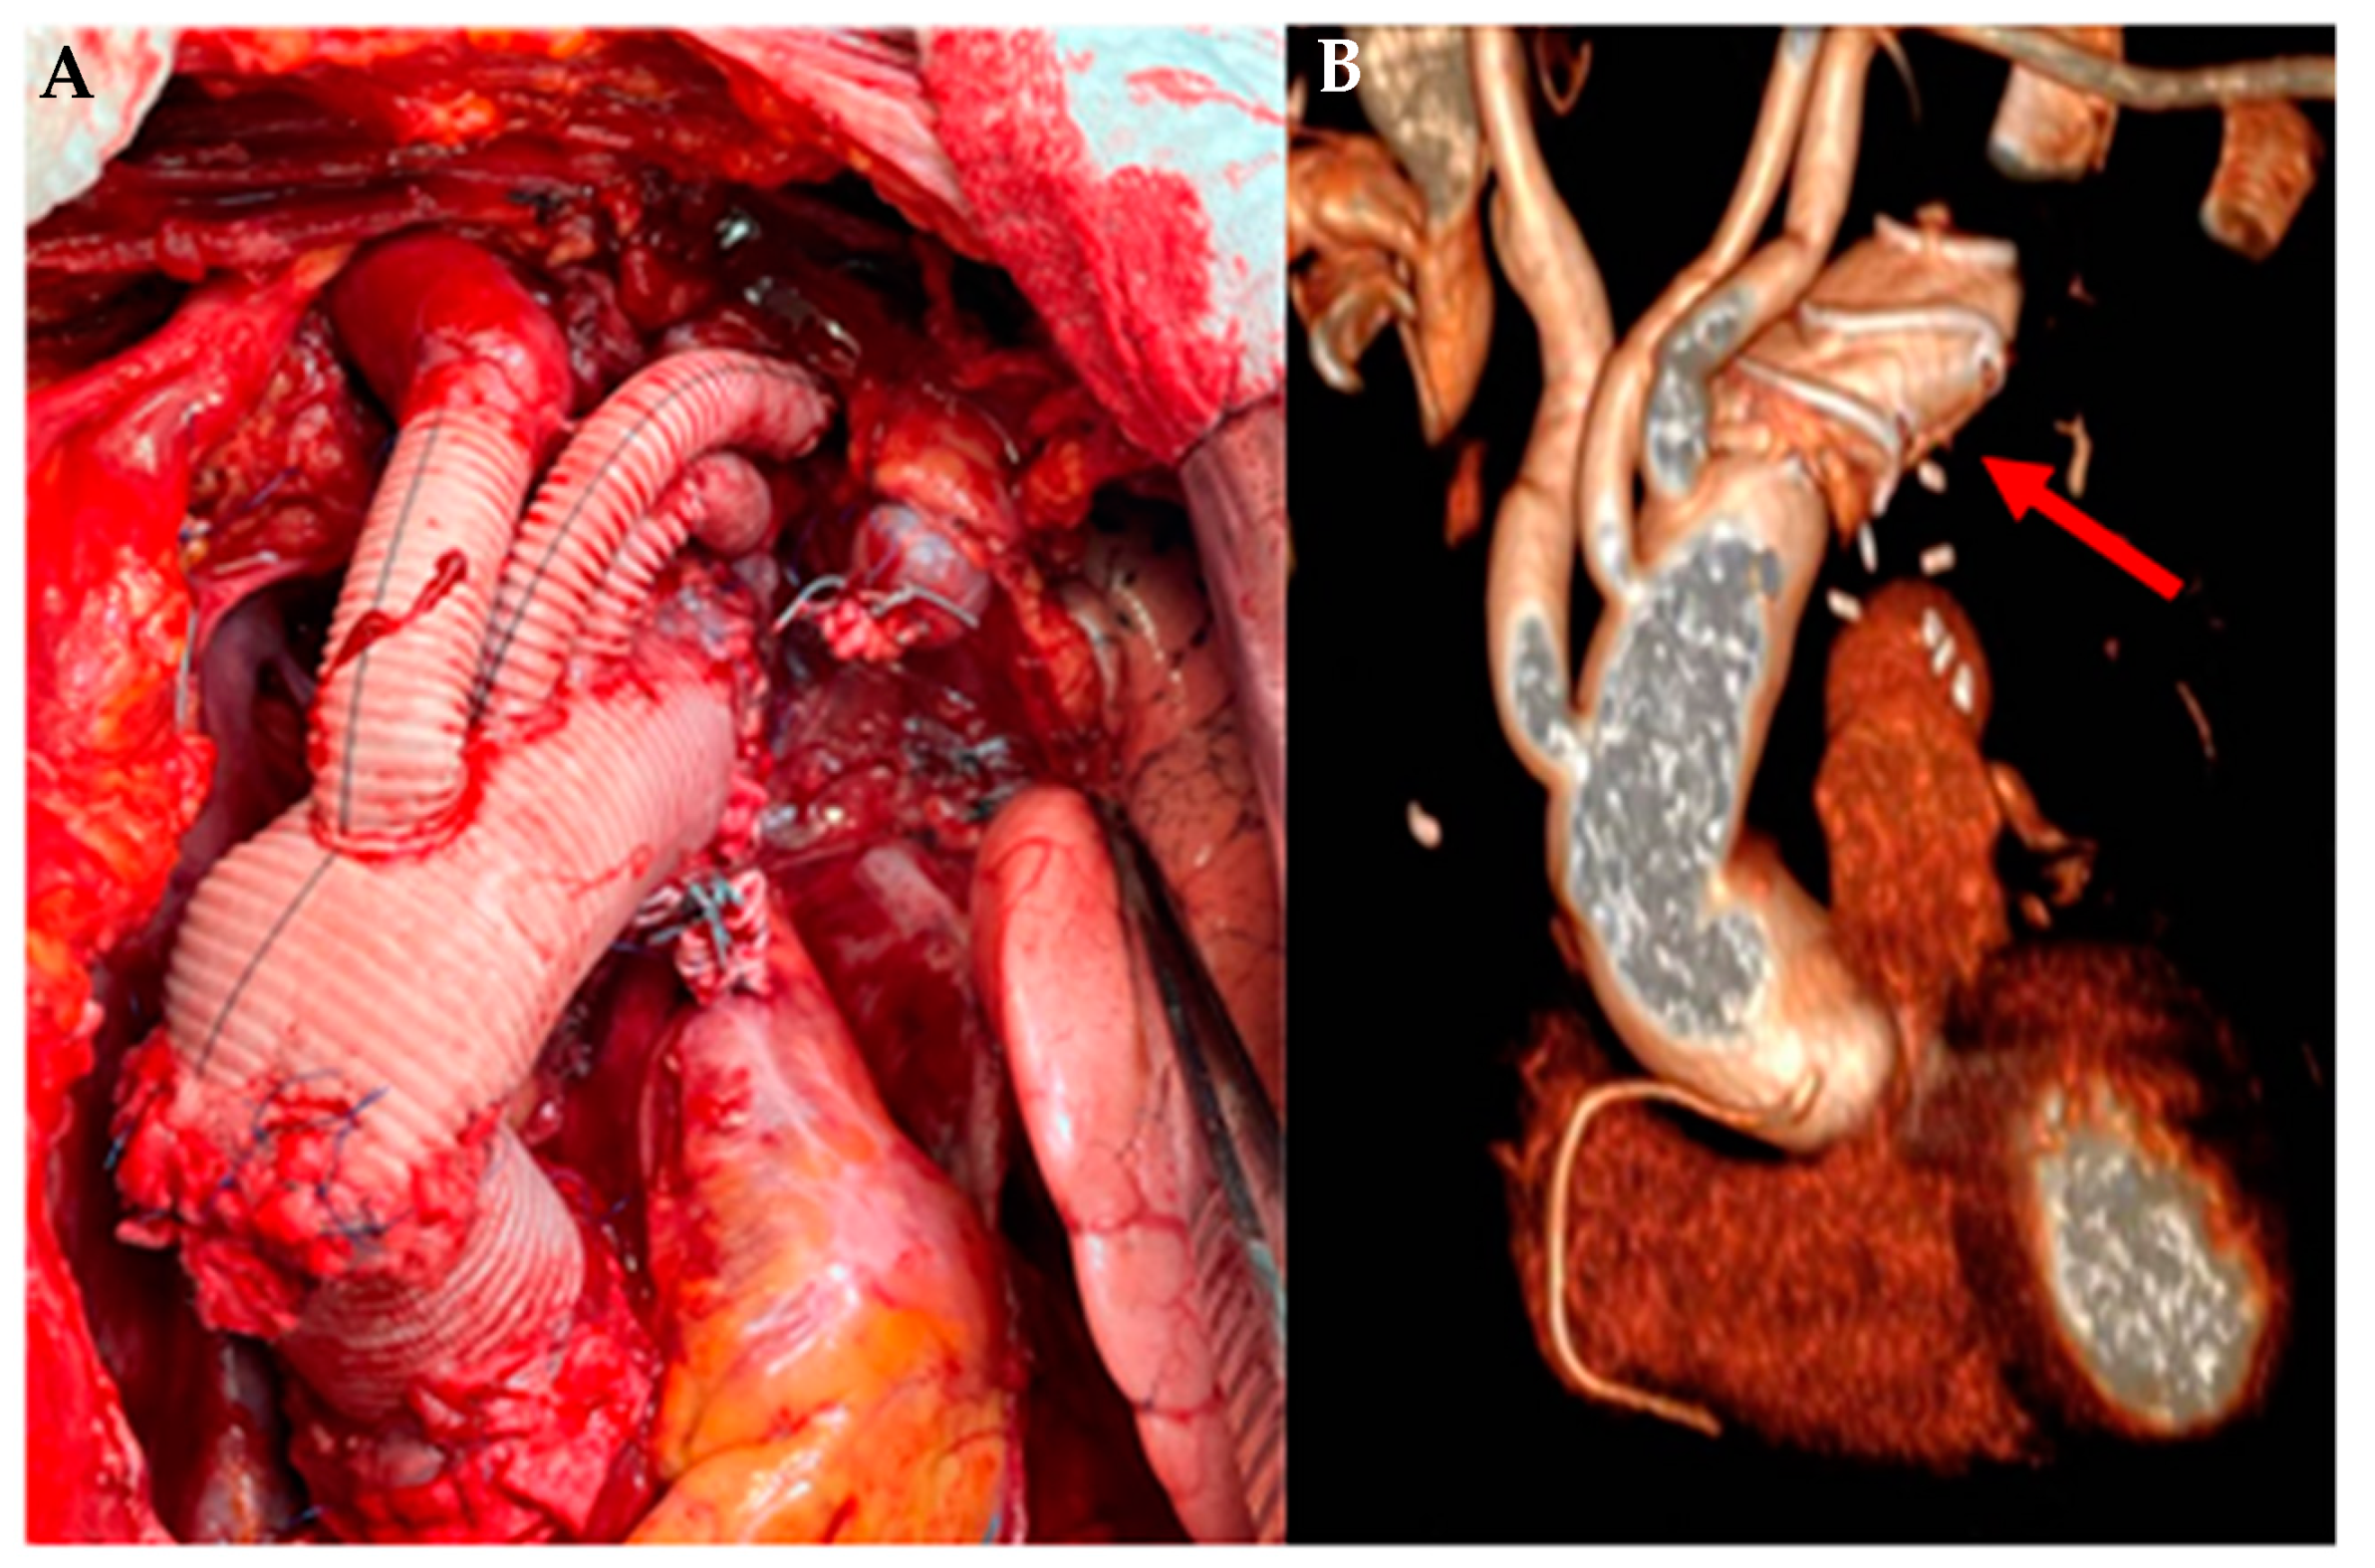

- Keschenau, P.R.; Kotelis, D.; Bisschop, J.; Barbati, M.E.; Grommes, J.; Mees, B.; Gombert, A.; Peppelenbosch, A.G.; Schurink, G.W.H.; Kalder, J.; et al. Editor’s Choice-Open Thoracic and Thoraco-abdominal Aortic Repair in Patients with Connective Tissue Disease. Eur. J. Vasc. Endovasc. Surg. 2017, 54, 588–596. [Google Scholar] [CrossRef]

- Widenka, K.J.; Kosiorowska, M.; Jakob, H.; Pacini, D.; Hemmer, W.; Grabenwoeger, M.; Sioris, T.; Moritz, A.; Tsagakis, K. Early and midterm results of frozen elephant trunk operation with Evita open stent-graft in patients with Marfan syndrome: Results of a multicentre study. BMC Cardiovasc. Disord. 2022, 22, 333. [Google Scholar] [CrossRef]

- Chen, Y.; Ma, W.G.; Li, J.R.; Zheng, J.; Li, Q.; Liu, Y.M.; Zhu, J.M.; Sun, L.Z. Can Frozen Elephant Trunk Cure Type I Dissection Confined to Thoracic Aorta in Marfan Syndrome? Ann. Thorac. Surg. 2020, 109, 1174–1182. [Google Scholar] [CrossRef]

- Jayarajan, S.N.; Downing, B.D.; Sanchez, L.A.; Jim, J. Trends of vascular surgery procedures in Marfan syndrome and Ehlers-Danlos syndrome. Vascular 2020, 28, 834–841. [Google Scholar] [CrossRef]

- Holscher, C.M.; Aridi, H.D.; Locham, S.S.; Hicks, C.W.; Canner, J.K.; Malas, M.; Black, J.H. Aortic Surgery Outcomes of Marfan Syndrome and Ehlers-Danlos Syndrome Patients at Teaching and Nonteaching Hospitals. Ann. Vasc. Surg. 2019, 55, 175–181.e3. [Google Scholar] [CrossRef] [PubMed]